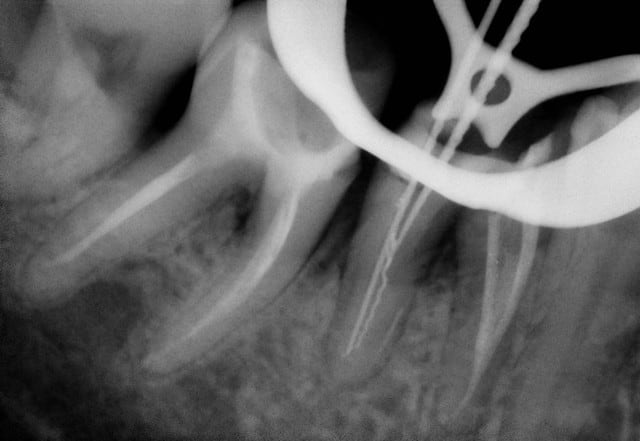

Voici un cas moins gentil avec élimination de la cause du problème pour reprendre les termes de Marc.

Il s'agit d'une patiente de 90 ans sur qui je reconstituais les secteurs postérieurs mandibulaires, ce qui fera l'objet d'un prochain post d'ailleurs, et dont un simple détartrage révélait la présence d'une énorme carie sous le pilier distal d'un bridge reliant la 23 à la 26.

Ayant intérêt à éviter de commencer un gros chantier alors qu'un autre était en cours, j'ai opté pour dégager et éliminer cette carie en conservant provisoirement ce bridge qui tenait bien, avant de traiter ce secteur en tachant de récupérer la racine de la 26 si possible.

J'ai déjà récupéré de nombreuses racines à ce stade et les ai utilisées comme piliers de bridges ou les ai couronnées, dans la mesure ou l'ancrage alvéolaire était solide et en respectant les furcations pour y assurer l'hygiène.

La gencive lasérisée devient très ferme avec le temps et le déchaussement se stabilise. Ces restaurations se comportent bien sur un recul de plusieurs années.

Un exemple: une 46 avec furcation linguale dénudée après lasérisation et restauration par une endocouronne céromère réalisée il y a 9 ans et sans signe clinique avec une excellente attache gingivale malgré la perte osseuse, les 3 avant dernières images ont été prises lors d'un contrôle en mars dernier ...

9 années pour cette patiente de 90 ans, cela vaut bien le coup d'essayer vous ne croyez-pas? (dernière radio)

Avec le laser, on devient bien plus conservateur...